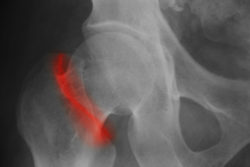

According to the Stryker LFIT hip replacement lawsuit, Peggy is a resident and citizen of the state of Delaware. She says that she was implanted with the LFIT Anatomic CoCr V40 Femoral Head on her right hip on April 5, 2011 at Saint Francis Hospital. She became implanted with the Accolade TMZF as the device’s femoral stem during the same procedure.

Howmedica Osteonics, a subsidiary of Stryker Orthopedics, are facing a multitude of lawsuits from patients alleging that they suffered severe adverse side effects and complications. Some reported side effects have included but have not been limited to: corrosion, metal toxicity, fretting, loss of bone fixation strength, hip stem fractures, and dissociation of the femoral head from the stem.

However, recognition of a failing hip replacement device has at times come much too late for many patients. For patients, like Peggy, they have only been able to confirm that their hip replacement device has failed after checking their blood for elevated levels of cobalt and chromium ions — indicative of a device that is shedding metal particles. As a metal-on-metal device, the LFIT V40 femoral head and TMZF femoral stem rub together, potentially releasing metal ions into the blood stream and surrounding tissues.